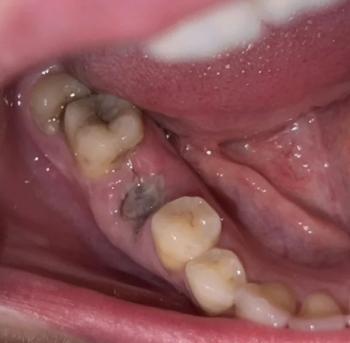

I see a dark, fairly deep socket behind the last visible molar (the extraction site).

No obvious pus or large swelling visible in the photo and you report no pain — both reassuring.

Surrounding teeth look intact. Photo lighting/angle limits how much I can see (I can’t check bleeding under the gum or feel for mobility).